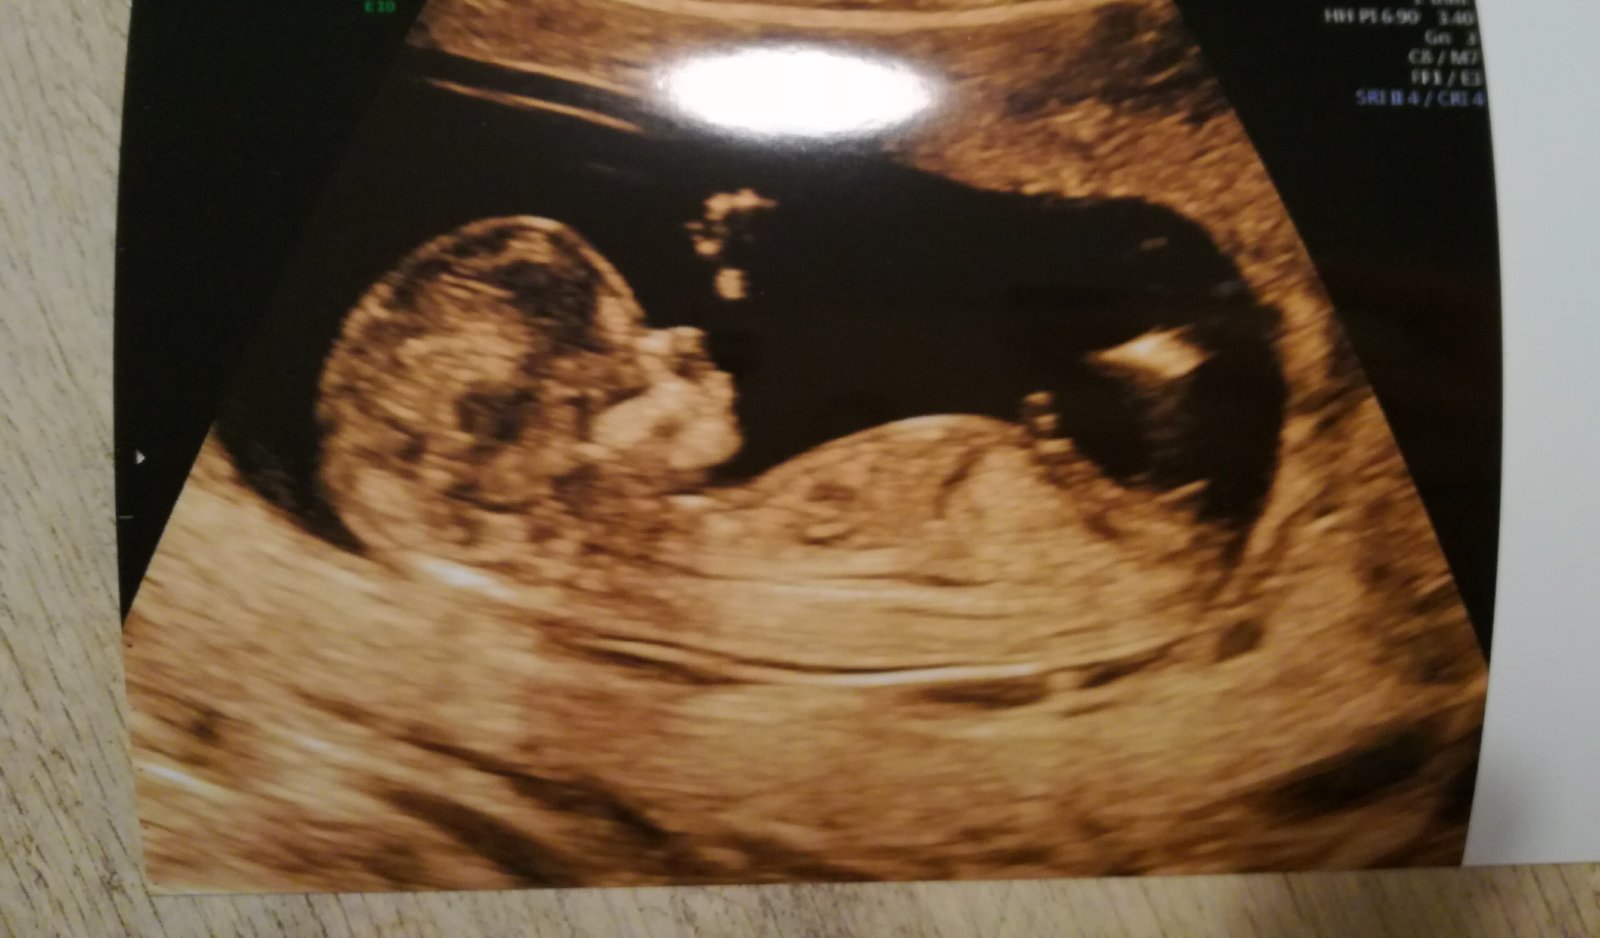

Přikládám foto ultrazvuku holčičky v 16tt pro ostatní maminky pro porovnani, je to zaber zespodu jakoby na prdku s roztazenyma nozkama 😉.

@mikejla_a ta tenká čárka v pravo dole by měl být pohl. hrbolek co směřuje nahoru 🙂

@fiendish.angel pokud je to za nožičkou pohlaví hrbolek tak by to měla týt holčička

@kristyna14092013 holčička. pohlavní hrbolek je souběžně s osou páteře. kdydy výrazně čněl nahoru, je to kluk 🙂